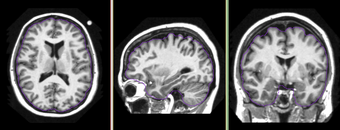

Input T1 Image